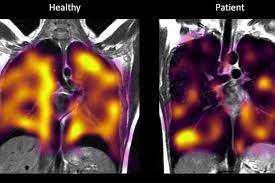

46.2KZdravljeOtkrivena skrivena oštećenja pluća kod dugog covida

Pacijenti koji osjećaju posljedice dugog covida imaju skrivena oštećenja pluća, navodi se u najnovijoj pilot studiji u Velikoj Britaniji.